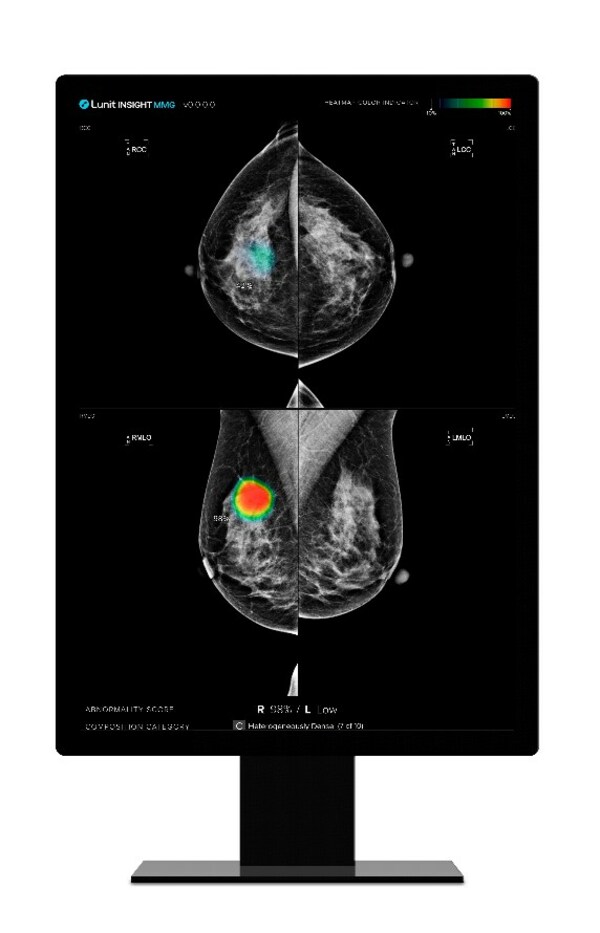

The Breast AI Analysis Package is a workflow-centric, evidence-based AI package part of Agfa’s RUBEE for AI framework, embedded in Agfa HealthCare’s Enterprise Imaging solution. Powered by Lunit INSIGHT MMG, the solution package helps improve radiologists’ screening and diagnostic workflow by providing advanced visualizations, workflow orchestration and triage benefits, dedicated reading protocols, and report notifications—thus helping early detection of breast cancer through cost-effective, quality diagnostic services.

Lunit INSIGHT MMG is one of Lunit’s most mature radiology products. The AI solution analyzes mammography images with high speed and 96% accuracy. By detecting suspicious lesions in mammography images, the AI solution helps radiologists distinguish suspected tumor areas by providing the location of the lesion with an abnormality score reflecting the AI’s confidence level.

“The Breast AI Analysis package provides powerful tools for cancer risk-based triage, along with natively embedded CAD AI visualizations and advanced 2D/3D mammography tools powered by Lunit INSIGHT MMG,” said Dr. Anjum Ahmed, Global Chief Medical Officer and the Director of Artificial Intelligence Innovations at Agfa HealthCare.